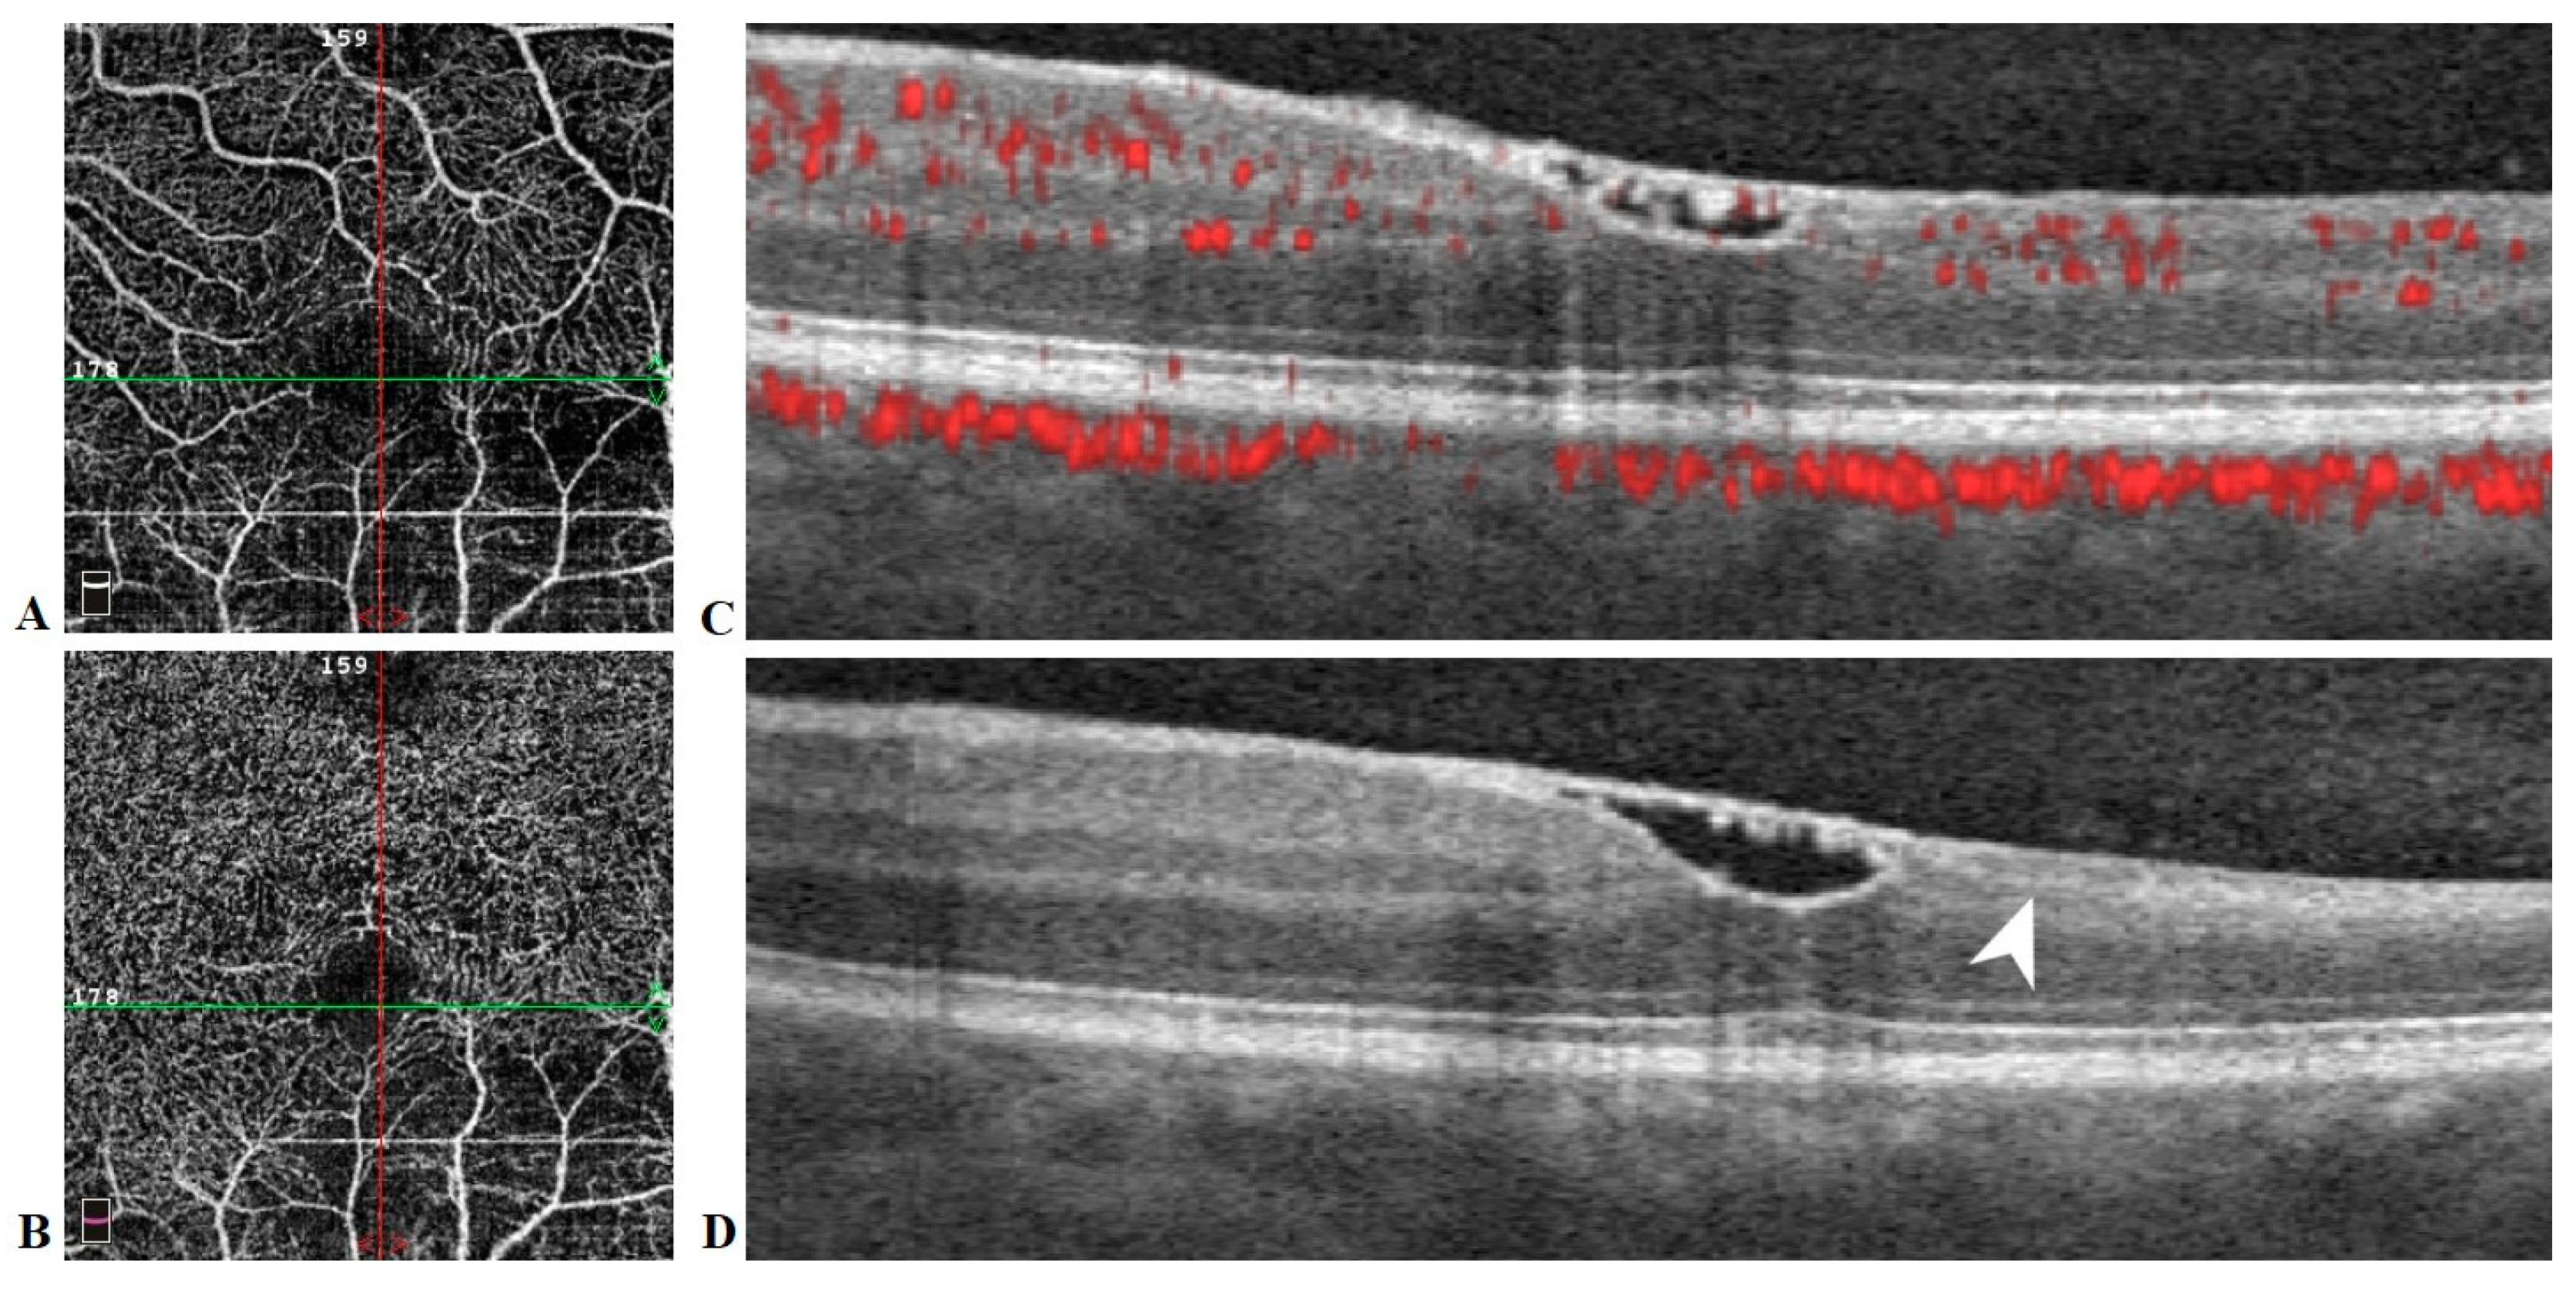

A 28-year-old woman with a history of migraines, prior tobacco use, narcolepsy, basilar artery occlusion (thought to be secondary to chiropractic manipulation) with resulting internuclear ophthalmoplegia without persistent defects, and asymptomatic left internal carotid artery (ICA) paraophthalmic aneurysm underwent a flow diversion procedure for the ICA aneurysm. She reported “I can’t see out of the top of my left eye” upon awakening in the postoperative care area. Emergency magnetic resonance imaging (MRI) showed no evidence of acute infarct, hemorrhage, or other intracranial abnormality. Magnetic resonance angiography/venography (MRA/MRV) revealed postprocedural changes of the left ICA but no other abnormalities of the intracranial vasculature (Figure 1).

Figure 1. Brain magnetic resonance angiography (MRA) immediately prior to ophthalmic examination shows anticipated changes from the recent revascularization procedure with persistent filling of the 2 mm supraclinoid segment aneurysm (arrowhead), without other abnormalities of the major intracranial vasculature.